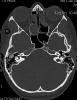

TC exostosis occipital congénica.

TC exostosis occipital congénita.